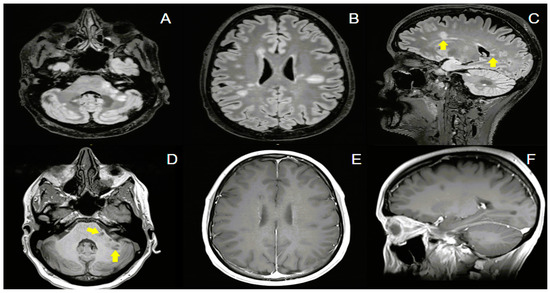

| Sterpi AE, et al. (2024) | 37/F | Breast Cancer | No | No | OLP, PLB, TRP, BVZ, LTR | IMRT | 30 | 10 | 2 months | Ataxia | Normal | No | Negative | Negative | Periventricular WM, corpus callosum, brainstem, cerebellum | - | IVMP with gradual tapering | Yes | No (6 months) | No new lesions (6 months) | N/A |

| Wong OY, et al. (2019) [31] | 31/F | Pituitary Macroadenoma | No | N/A | CBR | IMRT | 50.4 | 28 | 4 months | Decreased visual acuity, diplopia, facial numbness, tongue hemianesthesia | Normal | No | N/A | N/A | Subcortical WM, periventricular WM, brainstem, cerebellum | N/A | PSL | Yes | No (12 months) | No new lesions (12 months) | N/A |

| Borges A, et al. (2021) [26] | 28/M | Suprasellar Germinoma | No | No | CRB, ETP, IFS | WVRT | 24 | 15 | 4 months | Subjective cognitive impairment | Normal | Yes | Negative | Negative | Periventricular WM, subcortical WM, brainstem, cerebellum | + | No | Yes | No (12 months) | No new lesions (10 months) | N/A |

| Kemp S, et al. (2016) [29] | 65/F | Trigeminal Neuralgia | N/A | N/A | GBP | SRS | 90 | 1 | 3 months | Facial numbness, hemiparaesthesia, ataxia | Normal | Yes | N/A | N/A | TREZ | + | IVMP | Yes | Yes (10 months—left lower limb weakness, gait ataxia) | Periventricular WM, cervical spinal cord (10 months) | Fingolimod |

| Guillemin F, et al. (2020) [28] | 36/F | Pituitary Macroadenoma | No | N/A | N/A | SRS | 50.4 | 28 | 3 months | Dizziness, ataxia, nystagmus, left arm hypoesthesia | Normal | Yes | Negative | Negative | Brainstem, cerebellum, subcortical WM | + | IVMP | Yes | Yes (6 months—weakness Nystagmus) | Infratentorial lesions (6 months) | Beta-1A- Interferon |

| Esakia T, et al. (2021) [27] | 34/M | Nasophary-ngeal Carcinoma | No | N/A | CSP, 5FU | Focal RT | 66 | 33 | 2 months | Headache, ataxia, nystagmus | N/A | N/A | N/A | N/A | Cerebellum, periventricular WM | + | IVDEX with gradual tapering | Yes | No (24 months) | No new lesions (24 months) | N/A |

| Toljan K, et al. (2021) [30] | 41/M | Pituitary Macroade- noma | No | No | N/A | IMRT | 50.4 | 28 | 3 months | Diplopia, facial hemihypoesthesia, dysarthria, tongue numbness, ataxia, hemiparesis, single-sided hypoacusia | 13 cells/μL Protein: 50 mg/dL | No | Negative | Negative | Brainstem, cerebellum | + | IVMP followed by DEX | Yes | No (11 months) | No new lesions (11 months) | N/A |